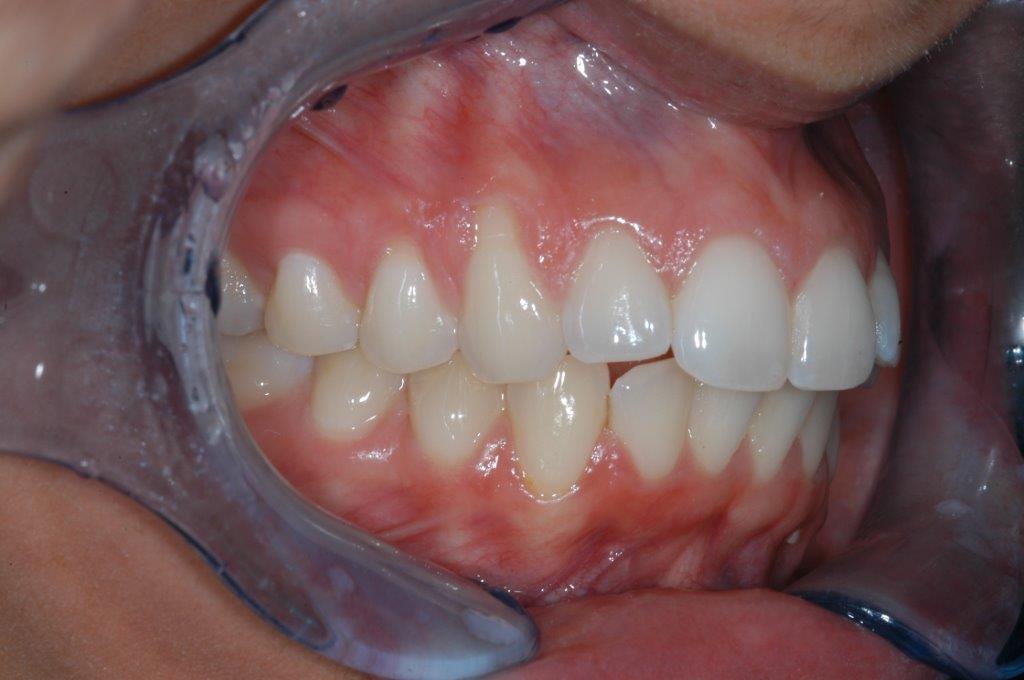

This patient experienced many areas of gum recession, primarily on the upper and lower front teeth. This patient's own tissue was used to correct the problem.